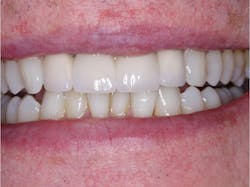

Currently, it is nearly impossible to avoid the use of ceramic crowns. Accomplish as much conservative intracoronal dentistry as possible, doing ceramic crowns only when necessary.

Do conservative tooth preparations on initial caries lesions. Although some political and commercial groups, as well as some dental organizations, are encouraging leaving small caries and waiting until the lesions are larger, my clinical observations over thousands of restorations and several decades of practice have convinced me that this is a flawed concept, especially for youth and young adults. Occasionally, it is somewhat acceptable for older persons who have had minimal lesions for many years. This concept is flawed not only from a tooth destruction standpoint, but also from an occlusal standpoint. When possible and with patient permission, treat initial caries for the same reasons I have expressed. The isthmus width for a molar class I or II composite restoration should be slightly wider than the width of a 330 bur. The isthmus width of a premolar should be about the width of a 329 bur. These conservative, disinfected preps allow most of the occlusion to remain on enamel, thus avoiding the collapse of occlusion caused by the unavoidable wear of composite restorations.